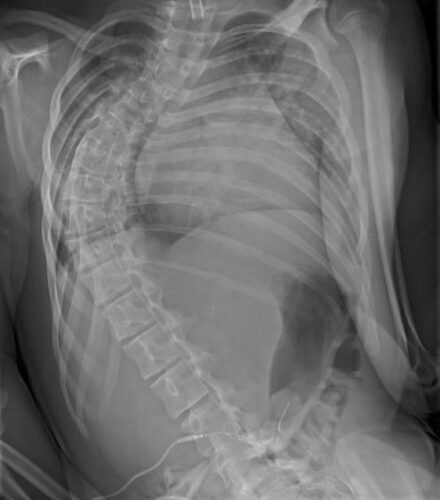

2. الأشعة السينية (X-ray): لقياس درجة الانحناء بدقة باستخدام زاوية كوب.

يُعد اعوجاج العمود الفقري العصبي العضلي من أكثر أنواع الجنف (انحناء العمود الفقري) تعقيدًا، ويأتي في المرتبة الثانية من حيث الشيوع بعد الاعوجاج مجهول السبب. هذا النوع يرتبط غالبًا بوجود أمراض تؤثر على الأعصاب أو العضلات مثل الشلل الدماغي، ضمور العضلات الشوكي، الحثل العضلي (دوشين)، السنسنة المشقوقة أو إصابات الحبل الشوكي.

يحدث هذا النوع من الاعوجاج عندما تفقد العضلات والأعصاب وظيفتها في دعم العمود الفقري والحفاظ على استقامته. فعندما تضعف العضلات أو تفقد التنسيق بسبب مرض عصبي أو عضلي، يبدأ العمود الفقري في الميل تدريجيًا، وقد يتطور بسرعة خاصة أثناء مرحلة النمو.